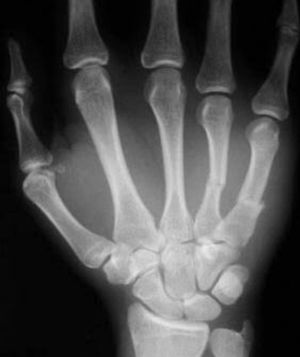

About the midlines of the fourth and fifth metacarpals

Mid shaft # of 4th and 5th metacarpal bones